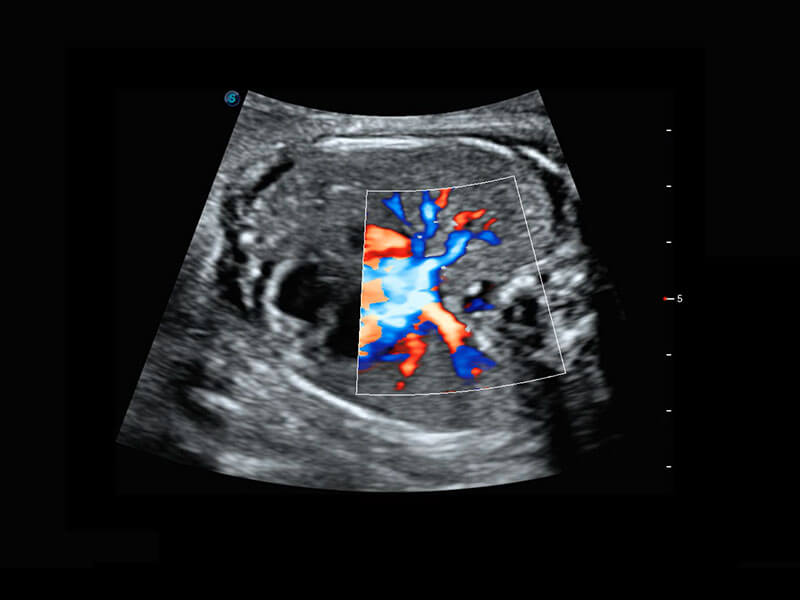

P60搭载一系列胎儿心脏成像技术,实现精细的胎儿心脏评估。

四腔心血流